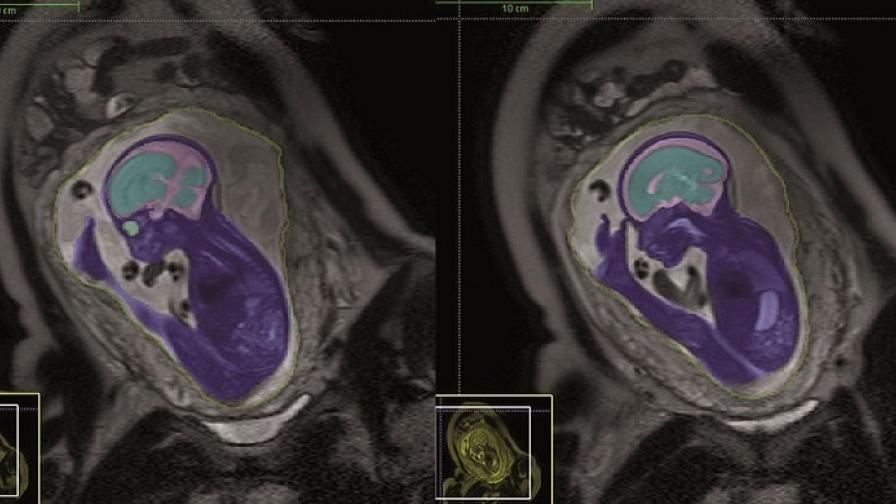

Saving unborn babies from brain damage with new MRI scanning techniques

Accurate 3D images can now be captured even when an unborn baby or the mother does not stay perfectly still and the process, which used to take 12 hours, now takes just 30 minutes.

Other organs, such as the heart and kidneys, can also be studied using this technique, which was developed by Professor Mary Rutherford and her team at Hammersmith Hospital, London (now St Thomas’s Hospital, London).